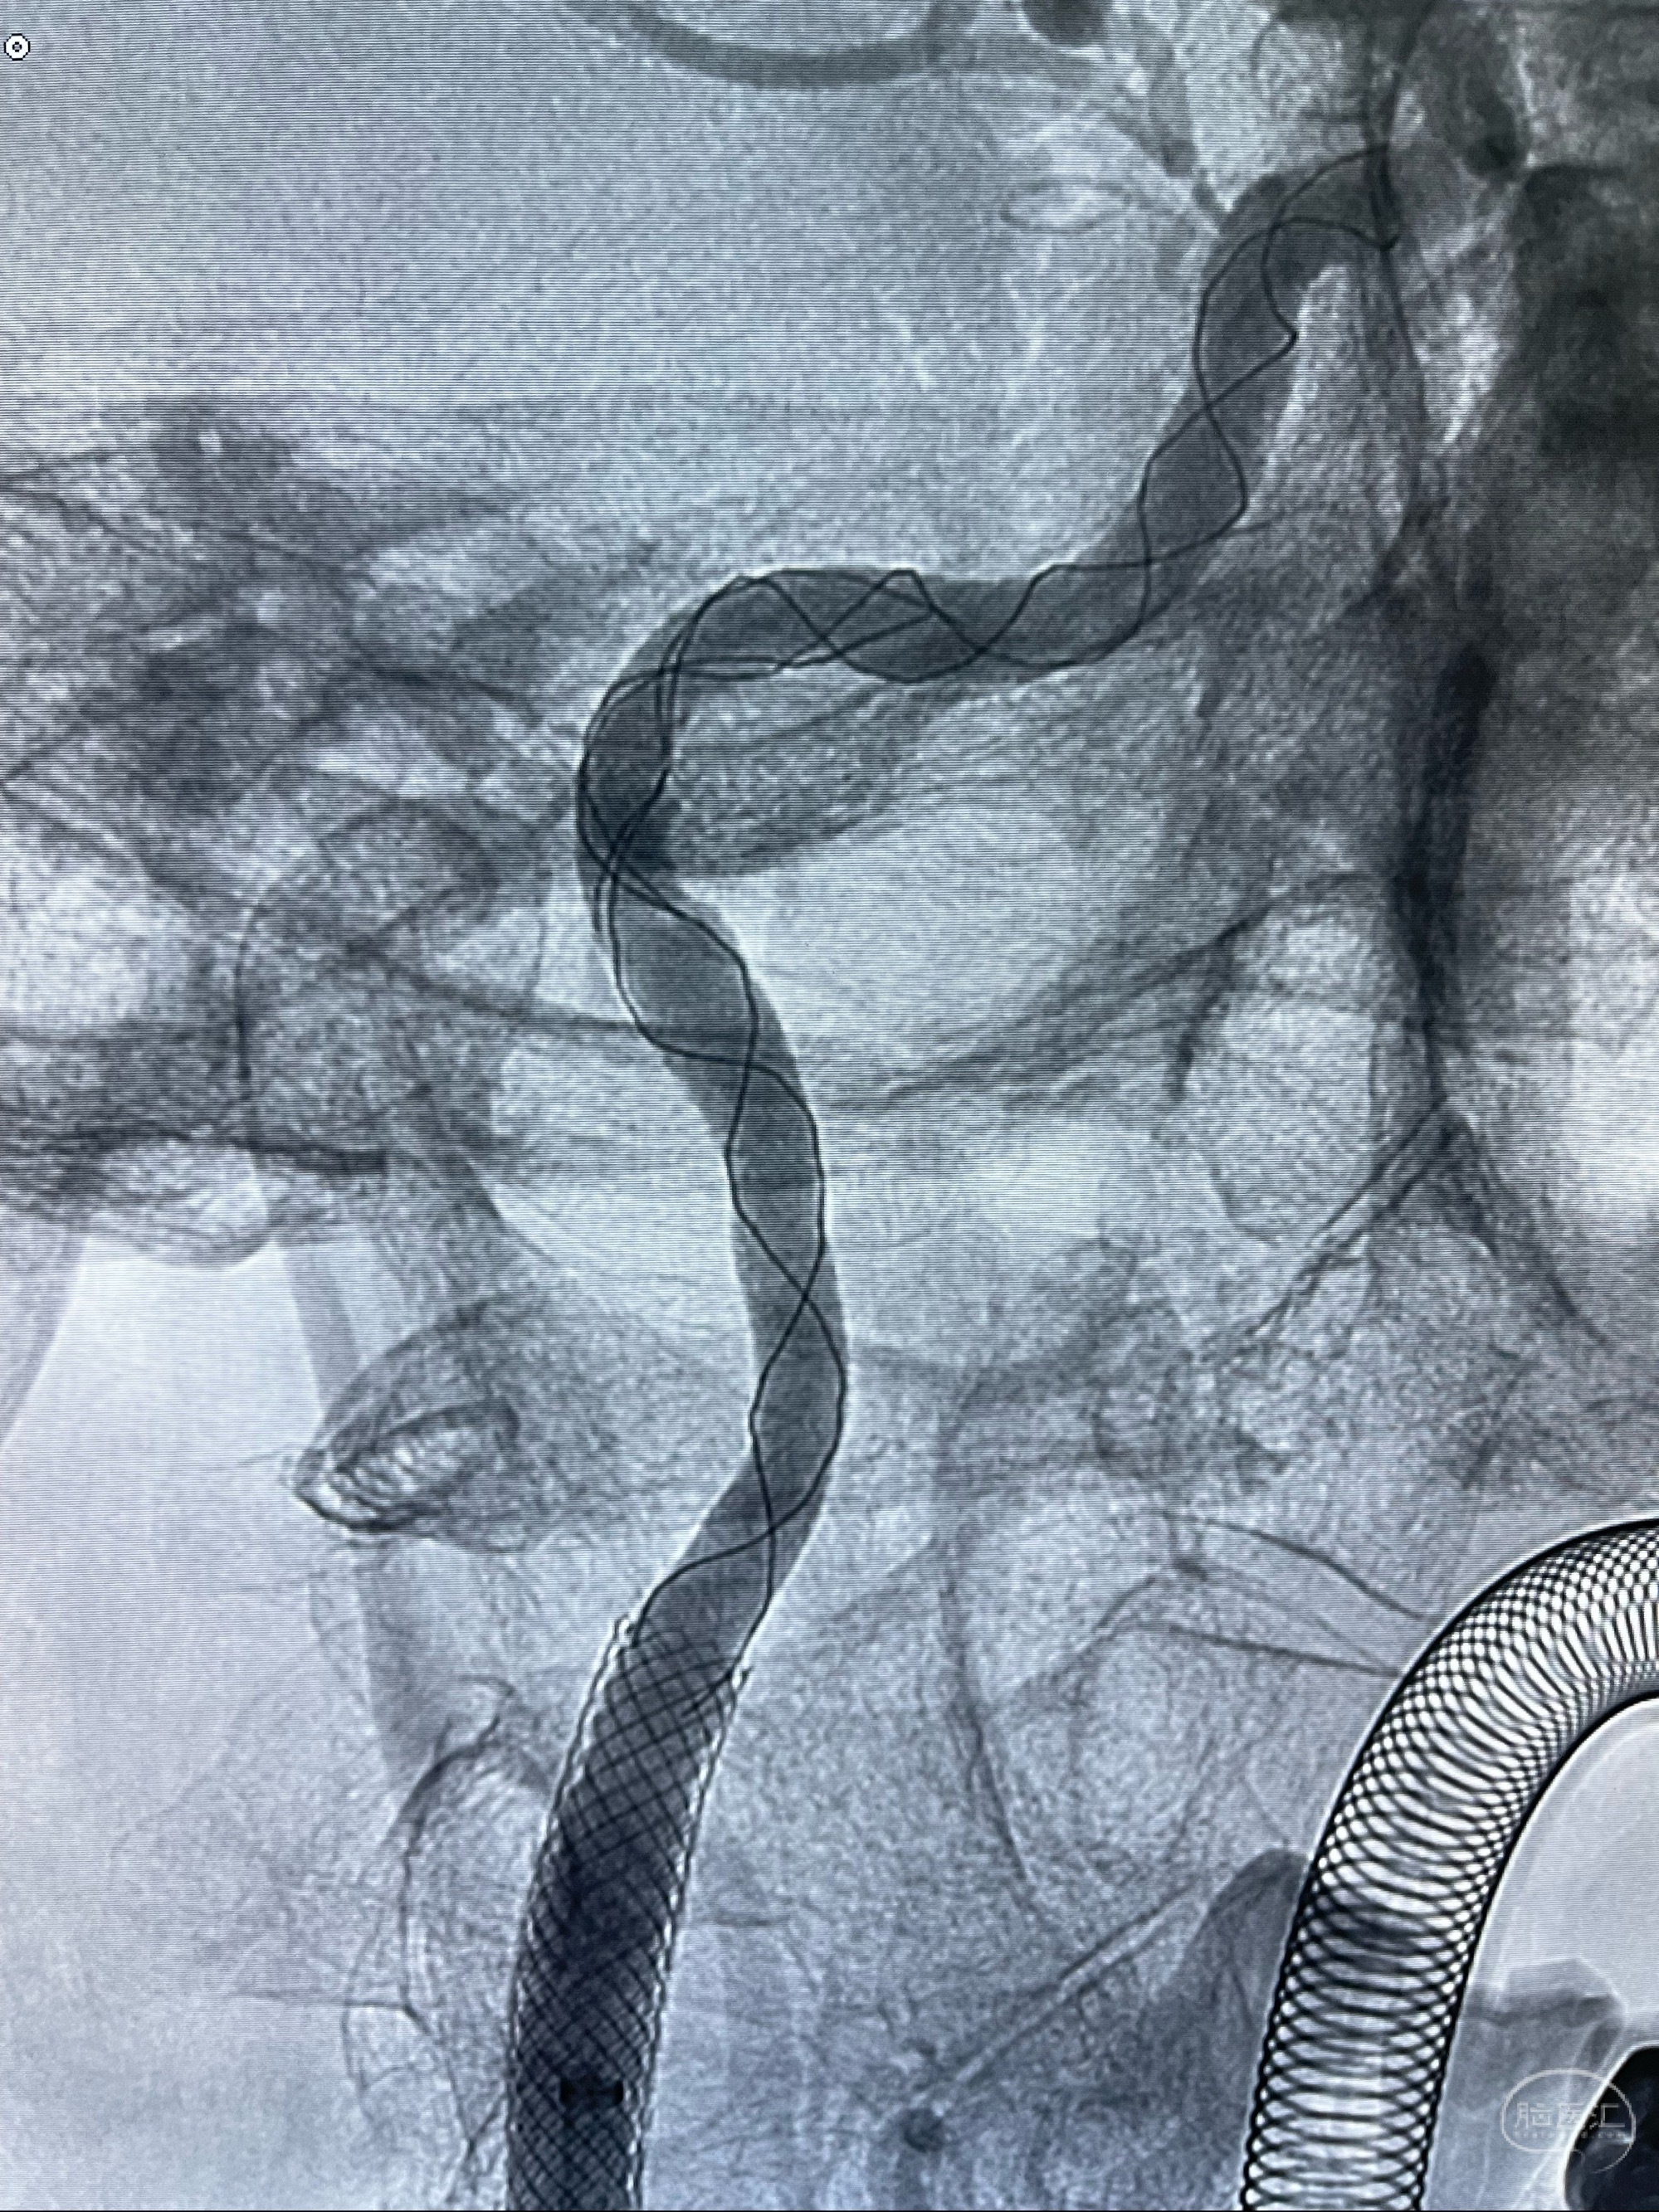

多次确认支架位置及打开贴壁情况

支架完全打开,近心端位于原颈动脉支架远心端内